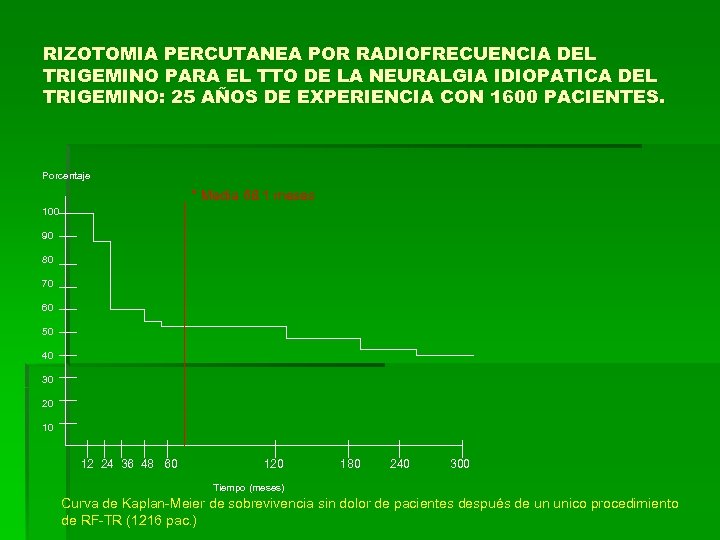

RIZOTOMIA PERCUTANEA POR RADIOFRECUENCIA DEL TRIGEMINO PARA EL TTO DE LA NEURALGIA IDIOPATICA DEL TRIGEMINO: 25 AÑOS DE EXPERIENCIA CON 1600 PACIENTES. Porcentaje * Media 68. 1 meses 100 90 80 70 60 50 40 30 20 10 12 24 36 48 60 120 180 240 300 Tiempo (meses) Curva de Kaplan-Meier de sobrevivencia sin dolor de pacientes después de un unico procedimiento de RF-TR (1216 pac. )

RIZOTOMIA PERCUTANEA POR RADIOFRECUENCIA DEL TRIGEMINO PARA EL TTO DE LA NEURALGIA IDIOPATICA DEL TRIGEMINO: 25 AÑOS DE EXPERIENCIA CON 1600 PACIENTES. Porcentaje * Media 68. 1 meses 100 90 80 70 60 50 40 30 20 10 12 24 36 48 60 120 180 240 300 Tiempo (meses) Curva de Kaplan-Meier de sobrevivencia sin dolor de pacientes después de un unico procedimiento de RF-TR (1216 pac. )